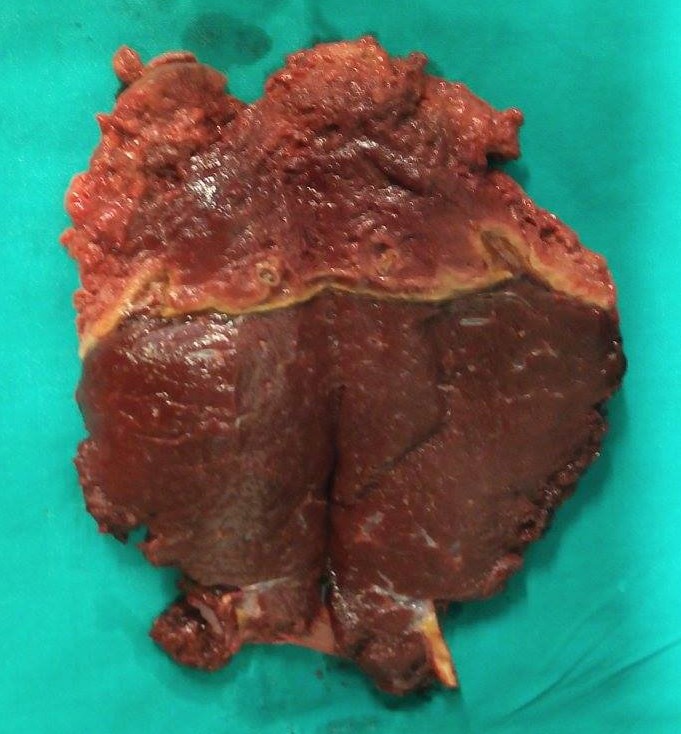

Liver after resection of the infected cyst. Presence of hemostatic Surgicel on the raw surface (Courtesy Dr. V. Penopoulos)